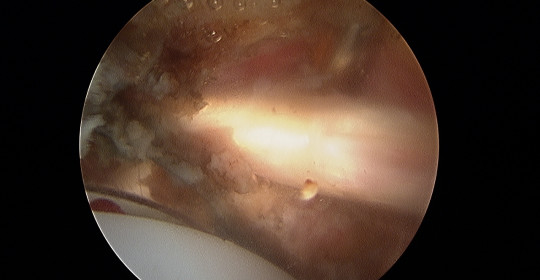

High satisfaction and low conversion rate to total hip arthroplasty after hip arthroscopy for femoroacetabular impingement syndrome and risk factors affecting survival at long-term follow-up

El propósito del estudio es la evaluación clínica del manejo capsular con tratamiento artroscópico del pinzamiento femoroacetabular y desgarros del labrum mediante la comparación de los resultados funcionales de la cápsula cerrada frente a la abierta.

Artículo publicado en la EFORT Open Review, la revista de la EFORT (European Federation of National Associations of Orthopaedics and Traumatology, en el que se expone la evidencia actual sobre la cirugía artroscópica de cadera.

Artículo publicado en la EFORT Open Review, la revista de la EFORT (European Federation of National Associations of Orthopaedics and Traumatology, en el que se expone la evidencia actual sobre la cirugía artroscópica de cadera.